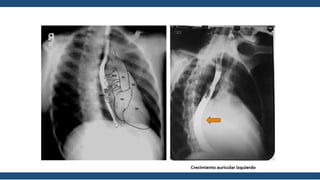

Radiografía de

Tórax

• Corazón generalmente de tamaño normal

• Perfil izquierdo con 4 arcos

• Aorta

• Pulmonar abombada

• Orejuela Izquierda prominente

• Ventrículo Izquierdo Normal

• En posiciones oblicuas

hay crecimiento de la AI

• Signos radiológicos de

hipertensión venocapilar

Moteado difuso

Hilios Pulmonares

Esfumados

Lineas A de Kerley

Lineas B de Kerley

Derrame Laminar

Infiltrados algodonosos

Guadalajara, J. F. (2012). Cardiología. CDMX: Mendez Editores.

Radiografía de Tórax • Corazóngeneralmente de tamaño normal • Perfil izquierdo con 4 arcos • Aorta • Pulmonar abombada • Orejuela Izquierda prominente • Ventrículo Izquierdo Normal • En posiciones oblicuas hay crecimiento de la AI • Signos radiológicos de hipertensión venocapilar Moteado difuso Hilios Pulmonares Esfumados Lineas A de Kerley Lineas B de Kerley Derrame Laminar Infiltrados algodonosos Guadalajara, J. F. (2012). Cardiología. CDMX: Mendez Editores.